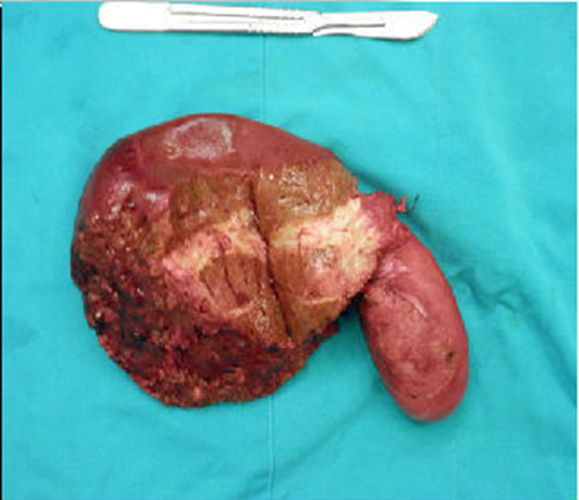

肝內膽管癌

肝內膽管癌後期症狀

肝內膽管癌末期